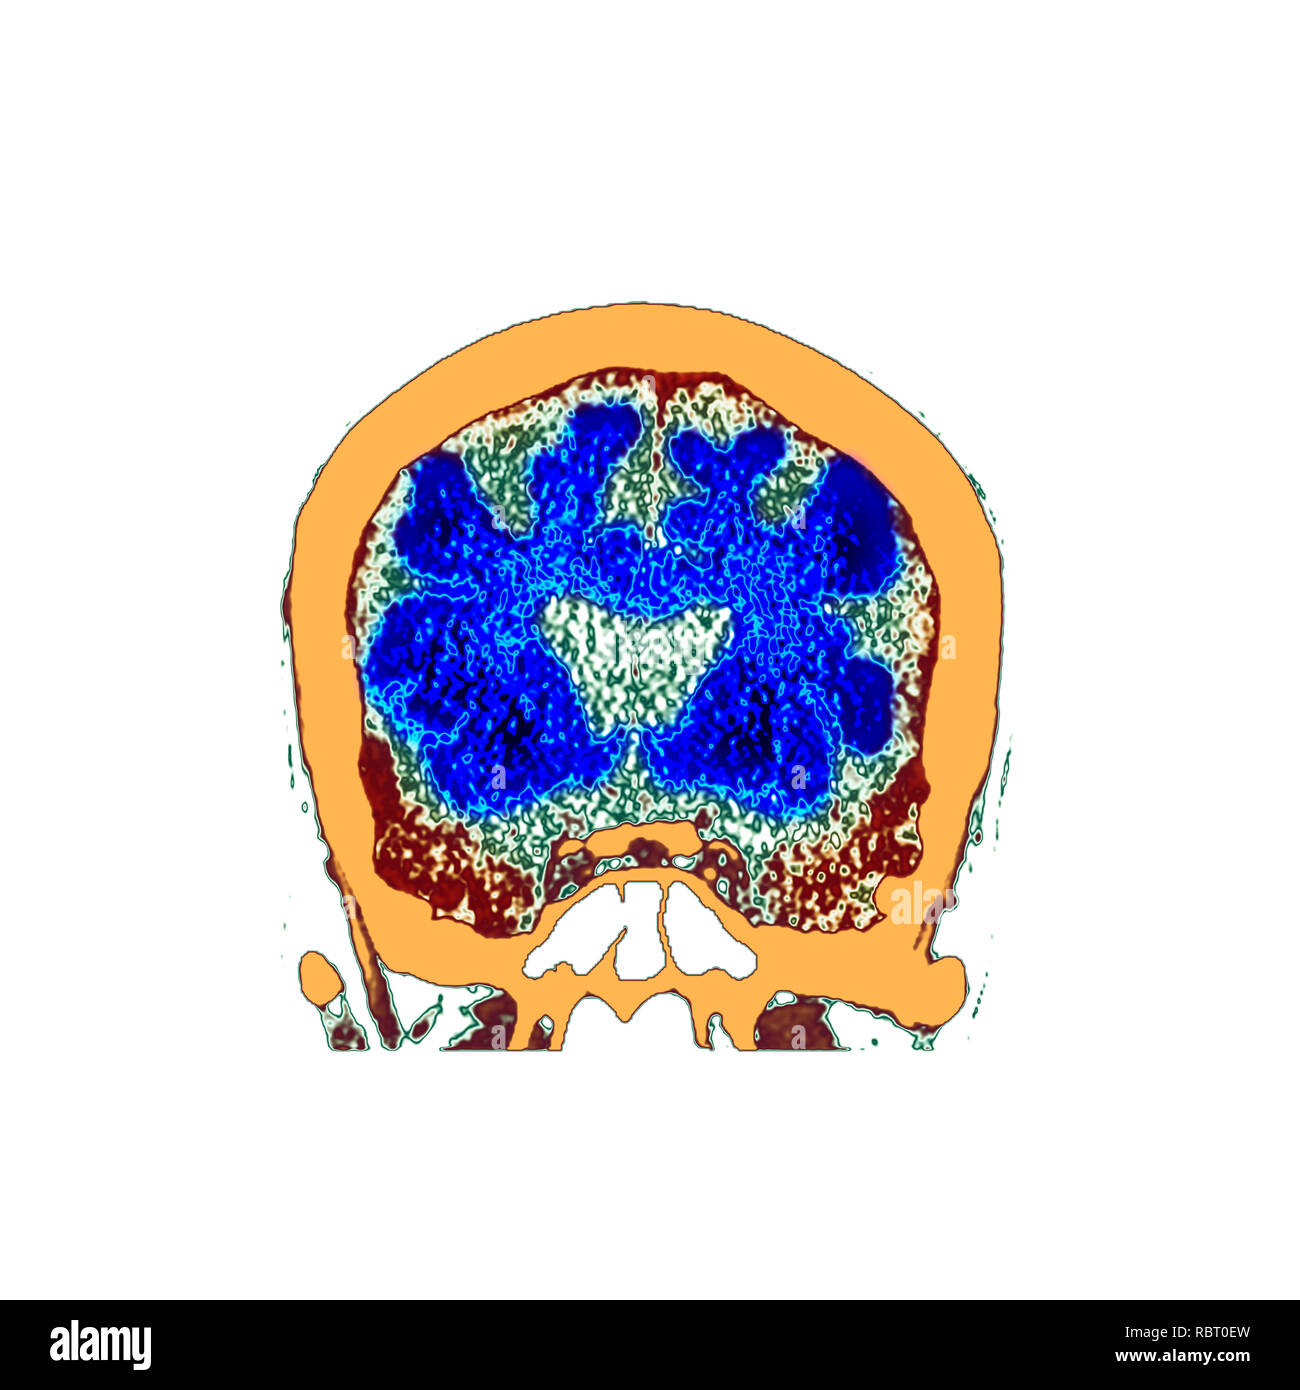

Alcoholic Dementia, Mri Scan Photograph by Du Cane Medical Imaging Ltd

Alcoholic Dementia, Mri Scan Photograph by Du Cane Medical Imaging Ltd

Alcoholic Dementia, Mri Scan Photograph by Du Cane Medical Imaging Ltd